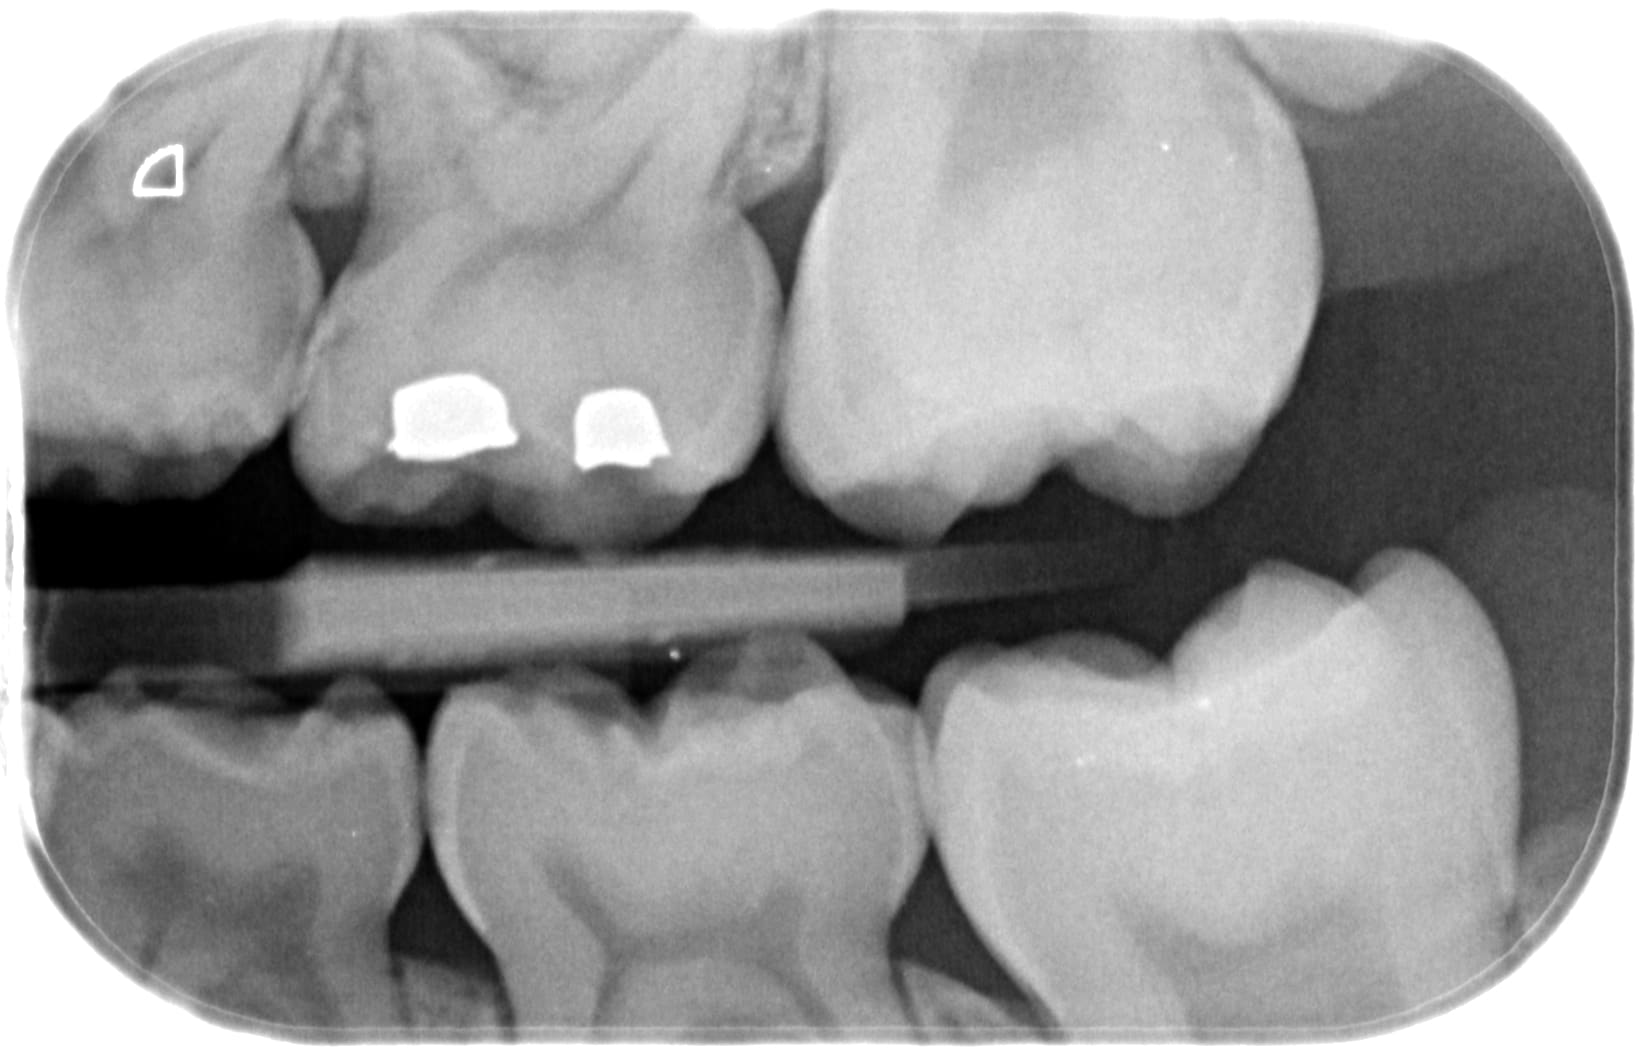

ce matin jour des enfants, je vois une jeune fille de 8ans pour la première fois...

Avant RA+10% = traitement CVIMAR des 3 caries proximales en deux séances...

Apres RA+10% = "Oh les belles dents... y'a une spicule de tartre bzim bzim... 30e, bonne journée"

t'as pas envie de ça ? on sangle et zou 8 coiffe pédo.